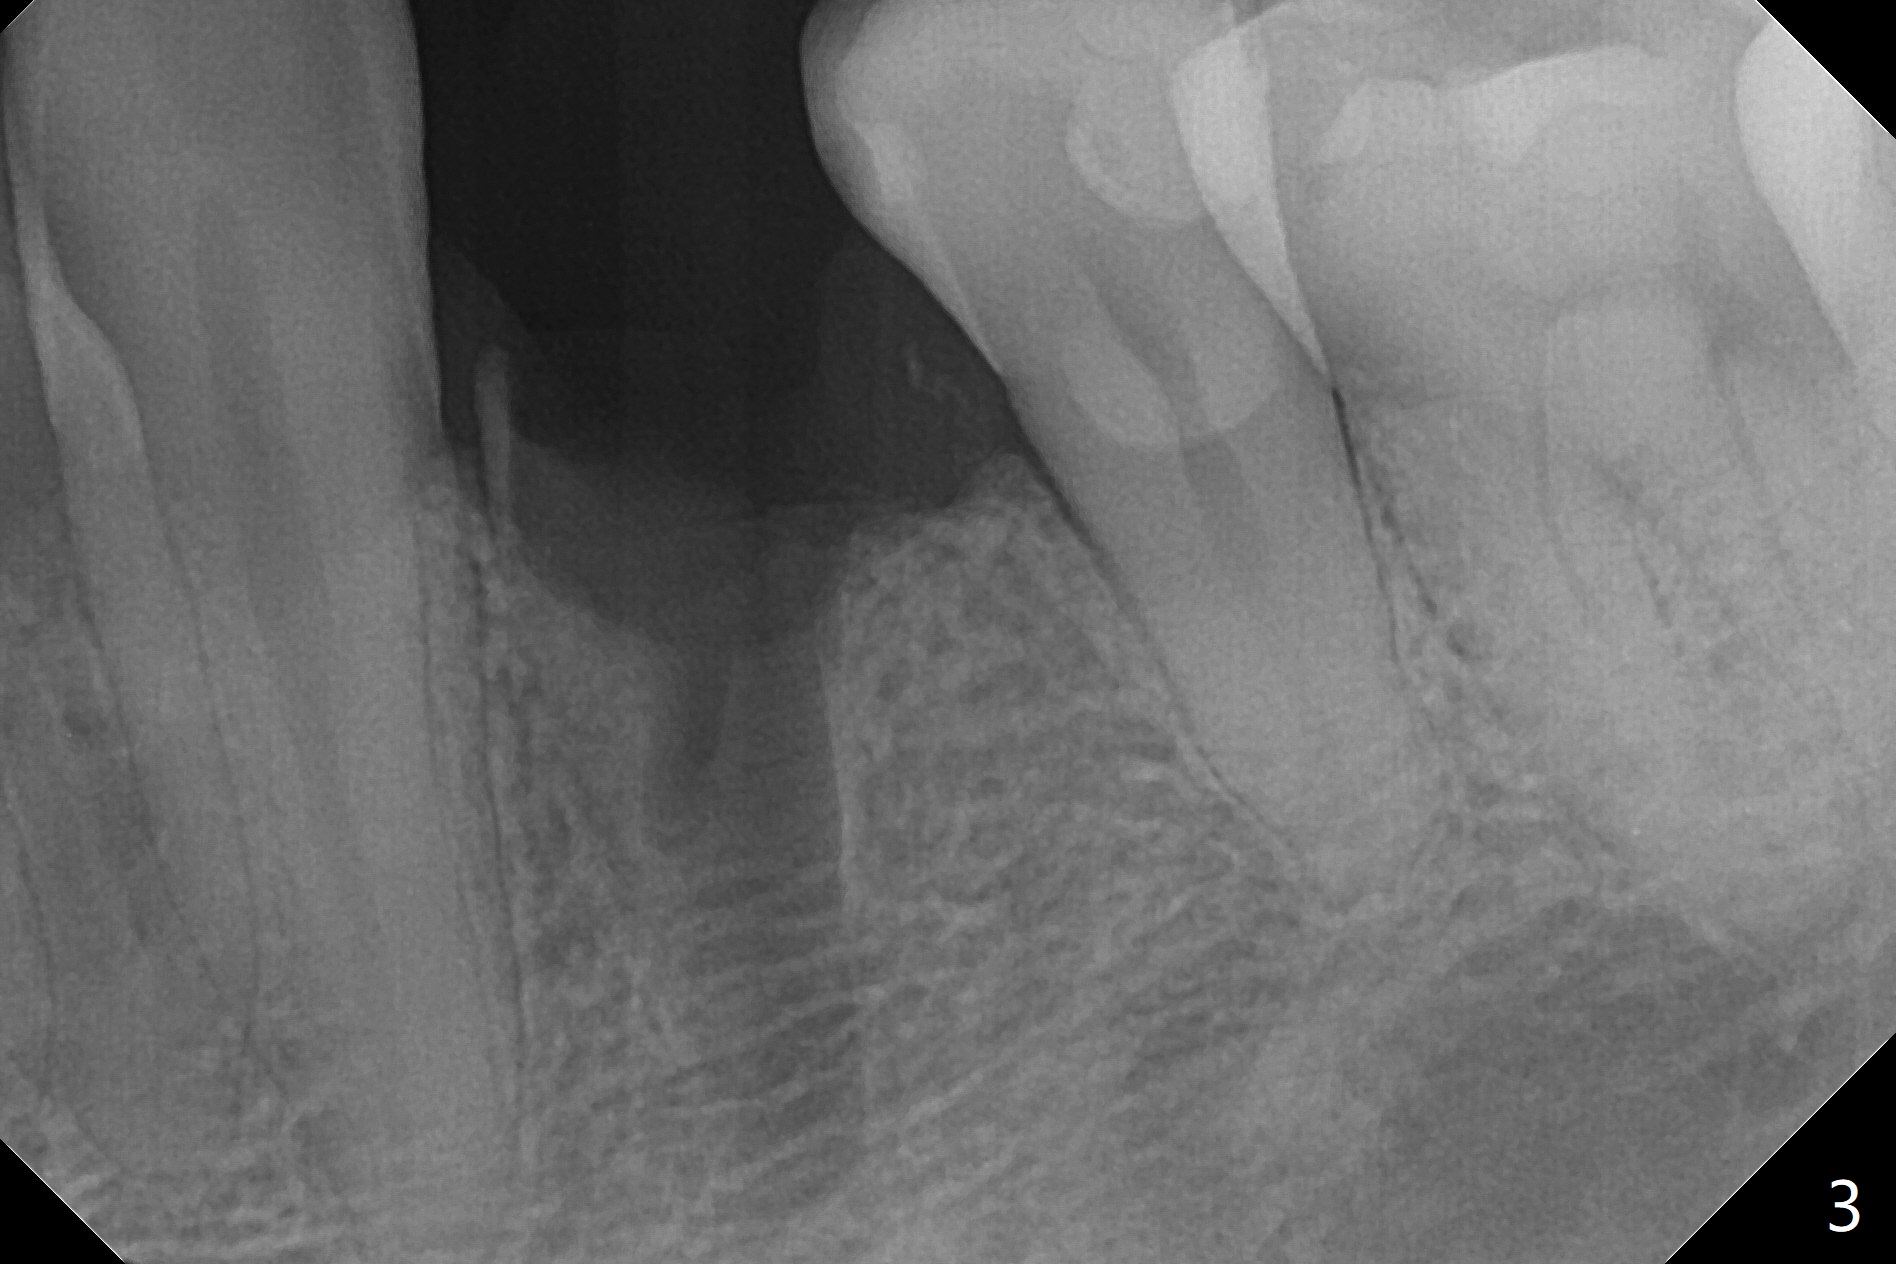

Three months post guide fabrication (coronavirus outbreak), the patient with loose post/crown returns for #21 extraction and immediate implant with guide (Fig.1 (*: post space)). In fact the root stump is flattened with diamond bur and 9 mm bone trimmer with guide before point drill. When the osteotomy finishes with 3.5x13 mm drill (under drilling with 10.5 mm offset), it has deviated buccal (Fig.2, 3,4); the outline of the bone trimmer mark is labeled by arrowheads in Fig.2. It appears that the center of the bone trimmer is dictated by that of the post space, as compared to Fig.1 *). When the root is removed except buccal shield (assuming that the deviation was due to the uneven surface of the root stump), the osteotomy is redone with guide, but remains buccal. Finally with buccal shield removal, a new lingual osteotomy is created free hand for a 4.5x11 mm implant (Fig.5) with 2-3 mm buccal gap for bone graft (Fig.6 * (literally)). In brief, bone trimmer also deviates according to resistance, basically irrelevant to the guide sleeve. The immediate provisional is intentionally removed 5 days postop to check whether a piece of gauze is retained in the socket as a gingival retraction cord for temporary crown fabrication; the buccal gap is kept with bone graft (Fig.7 *). No foreign body is in place. The margin of the abutment seems quite subgingival (Fig.8 *), but re-trimmed and polished provisional looks harmonious with the surrounding gingiva and the opposing dentition (Fig.9,10). The patient returns for prophy 2 months postop; the immediate provisional is removed for trimming and polishing. The bone graft seems to be integrated into a part of the gingiva (Fig.11 >). The abutment cuff appears to be too short.